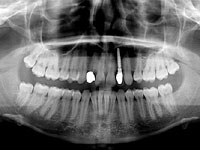

Einzelne Zähne können auch in völlig gesunden Gebissen durch Unfall oder Entzündungen verloren gehen, ebenso sind besonders die oberen seitlichen Schneidezähne häufiger nicht angelegt. Die drei Bilder zeigen den Ersatz eines nicht angelegten seitlichen oberen Schneidezahnes bei einem Jugendlichen.